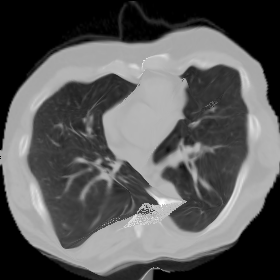

Figure 9. The lung CT example.

7.3. Real CT images

We now consider applying the proposed image registration method on real lung CT images retrieved from the National Lung Screening Trial (NLST) dataset [1]. Fig. 9(a) and Fig. 9(b) show two slices of lung CT images that we use as the source and the target (see Fig. 9(c) for the absolute intensity difference). We remark that the CT images are originally with different intensity, and so we apply an intensity histogram matching before running the registration experiment. Fig. 9(d) shows the registration result obtained by our proposed method. It can be observed that our method successfully produces a large deformation on the right lung of the source image to match that of the target image (see also Fig. 9(e) for the final absolute intensity difference). On the contrary, DDemons [47] (Fig. 9(f)), LDDMM [5] (Fig. 9(g)), Elastix [29] (Fig. 9(h)) and DROP [18] (Fig. 9(i)) all fail to produce an accurate and bijective registration result. This shows that our method is more capable of handling large deformation image registration.